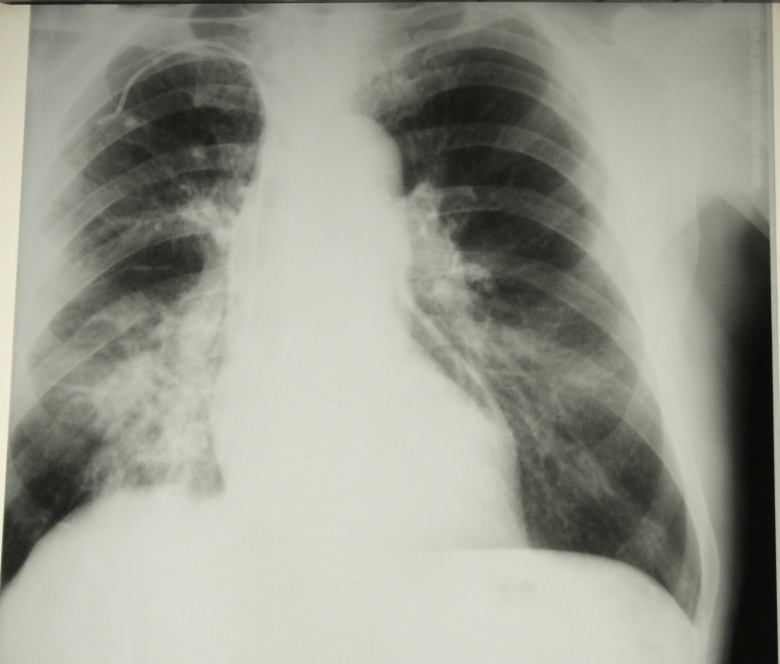

Заголовок сообщения: Пневмоперикард

Обсуждали здесь viewtopic.php?f=24&t=2574